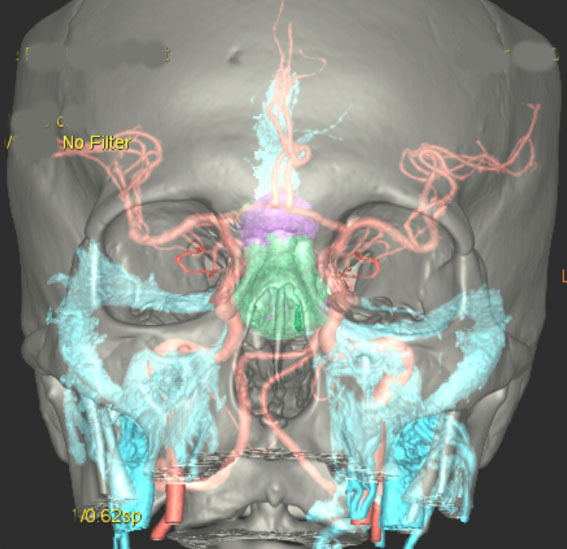

頭蓋骨を透して下垂体腺腫を見たものです。両目の間,頭の中心に緑色に塗ったのが下垂体腺腫です。頭蓋底の鼻腔の奥にあるともいえます。赤い色は動脈,青い色は静脈で,多くの血管に囲まれています。